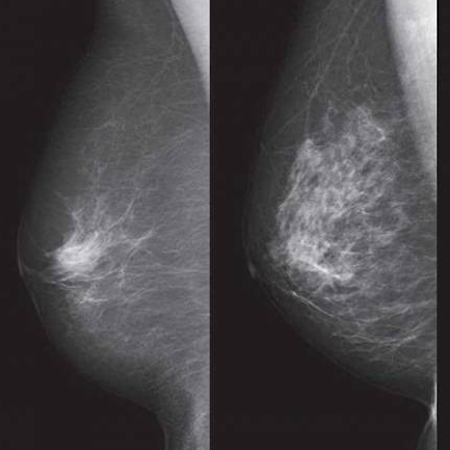

Using a deep learning model for lung cancer survival and outcome predictions can have potential clinical implications on adaptive and personalized therapy.